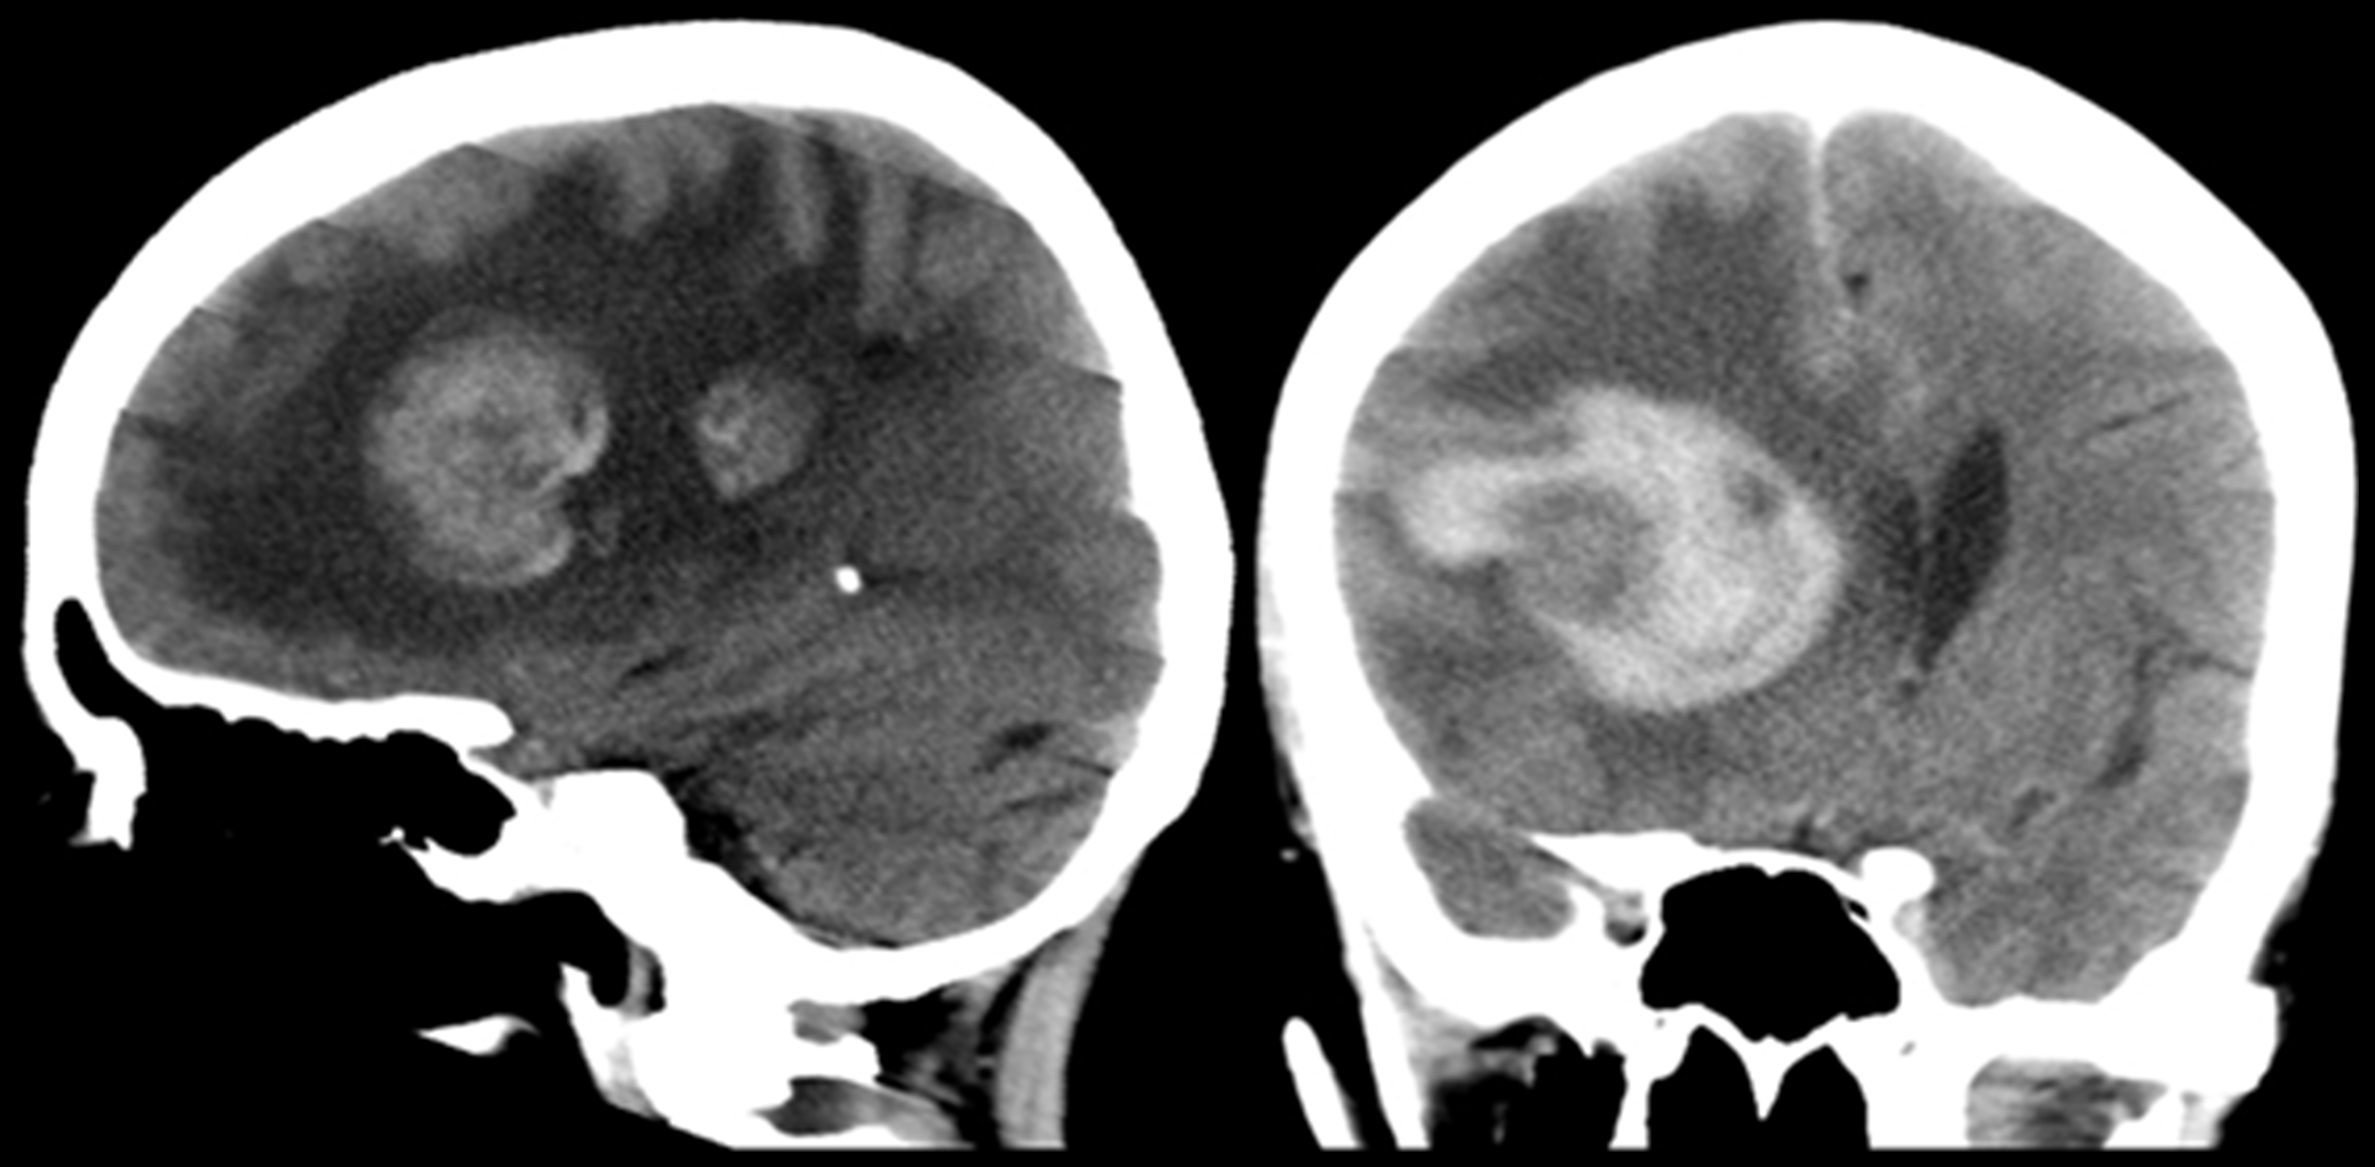

Se realiza TC de cráneo (Fig. 1), donde se constata la presencia de dos lesiones intra-axiales frontales derechas, con sectores espontáneamente hiperdensos en relación a sangrado. Ambas presentan realce en anillo grueso e irregular con el medio de contraste. En RM son de intensidad de señal heterogénea, hipointensas en T2/FLAIR (del inglés “fluid attenuated inversión recovery”), hiperintensas en T1, con realce periférico grueso, continuo e irregular con gadolinio. En secuencias eco de gradientes (GRE) se observan zonas de artificio de susceptibilidad magnética en relación a áreas de sangrado interno. En difusión-ADC (coeficiente de difusión aparente) se objetivan áreas periféricas de restricción y en el estudio de perfusión disminución del volumen sanguíneo cerebral (Fig. 2). Se completó estudio con TC de cuello, tórax, abdomen y pelvis, sin identificarse lesiones sugerentes de compromiso nodal, hepático o esplénico.

Figura 1

a) Tomografía sin contraste. Se observa lesión intra-axial frontal derecha, con sectores espontáneamente hiperdensos en relación a sangrado, y otra lesión menos evidente frontal anterior isodensa con respecto a la sustancia gris. Gran cantidad de edema locorregional y severo efecto de masa, con desviación significativa de la línea media.

b) Tomografía con contraste. Se delimita con mayor claridad la lesión frontal anterior, con 1a 1b realce en anillo continuo, grueso e irregular.